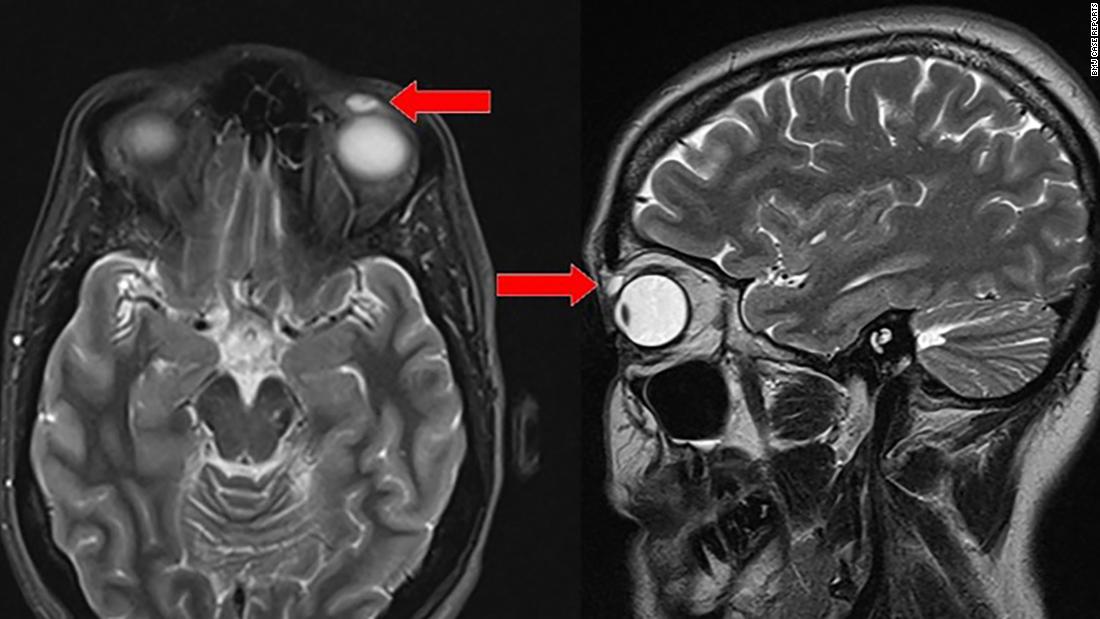

Empezó como un bulto del porte de un poroto, justo abajo de su párpado izquierdo. Luego el quiste creció durante un periodo de seis meses hasta que fue visible en una resonancia magnética. Además de la hinchazón y el posterior dolor al tocarlo, su párpado comenzó a caerse.

Cuando los cirujanos descubrieron el con el lente rígido, estaba intacto: parecía haber estado perfectamente encapsulado por el tejido. En el proceso de removerlo, el lente estaba quebrado y astillado.